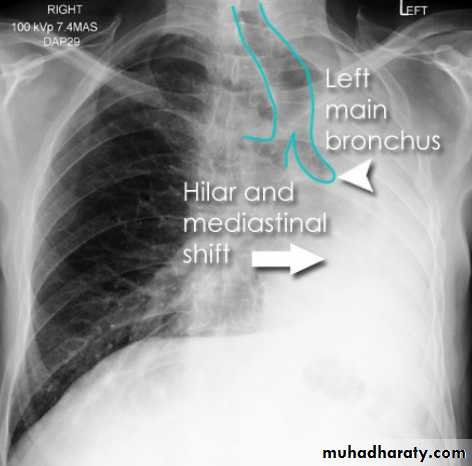

Left upper lobe collapse has distinctive features but can be challenging to identify on chest radiographs by the uninitiated.

Radiographic features

The left upper lobe collapses anteriorly becoming a thin sheet of tissue apposed to the anterior chest wall, and appears as a hazy or veiling opacity extending out from the hilum and fading out inferiorly . It thus reverses the normal slight increase in radiographic density seen as you move down the lung (due to increased thickness of the chest soft tissues).

Parts of the normal cardiomediastinal contour may also be obliterated where the left upper lobe, particularly the lingula abut the left heart border. The anterior parts of the aortic arch are also often obliterated from view.

In some cases the hyperexpanded superior segment of the left lower lobe insinuates itself between the left upper lobe and the superior mediastinum, sharply silhouetting the aortic arch and resulting in a lucency medially. This is known as the luftsichel sign.

The left hilum is also drawn upwards, resulting in an almost horizontal course of the left main bronchus and vertical course of the left lower lobe bronchus.

Non-specific signs indicating left sided atelectasis will also be present, including:

elevation of the hemidiaphragm

'peaked' or 'tented' hemidiaphragm: juxtaphrenic peak sign

crowding of the left sided ribs

shift of the mediastinum to the left

On lateral projections the left lower lobe is hyperexpanded and the oblique fissure displaced anteriorly. There is associated increase in the retrosternal opacity.